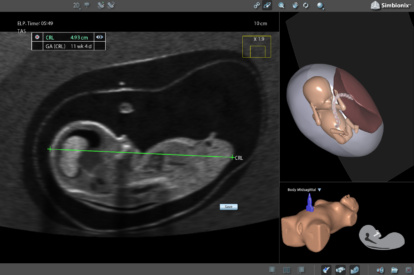

Ultrasound Mentor accelerates the development of basic to advanced technical and cognitive skills, by providing not only the probe manipulation training, but also a didactic environment enabling structured, self-guided learning including step-by-step instructions and educational aids such as 3D anatomical map and probe positioning assistant, all backed up with our progress monitoring tool MentorLearn.

- Advanced diagnostic tools, including Color Doppler, CW, PW, M-mode, and measurements

OB 2nd Trimester Module